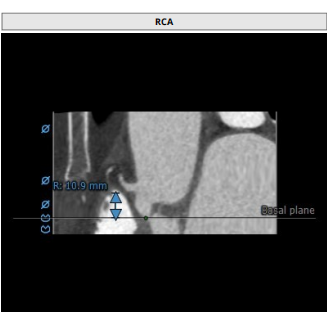

瓣叶增厚 右冠高度:10.9mm

左冠高度:9.5mm

患者为三叶瓣,左右、右无疑似粘连,瓣叶明显增厚,轻度钙化。右冠高度10.9mm,左冠高度9.5mm,冠脉高度均较低。法式窦小,心脏角度不大,左室大小可,升主动脉未见明显增宽,病人整体结构小,瓣环仅有16.9mm,左室流出道16.7mm,窦管结合部23.9mm,升主动脉31.4mm。选择右股作为主入路。